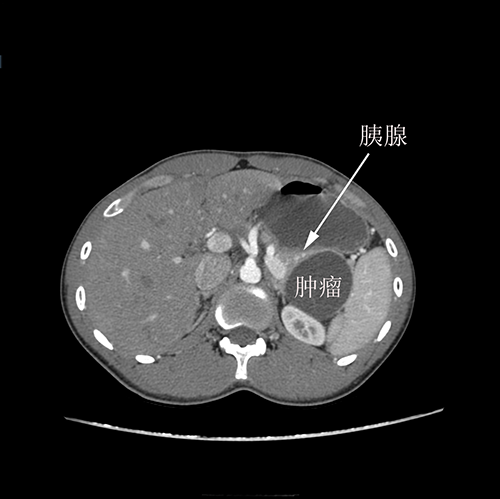

胰尾囊腺瘤---腹腔镜胰尾切除